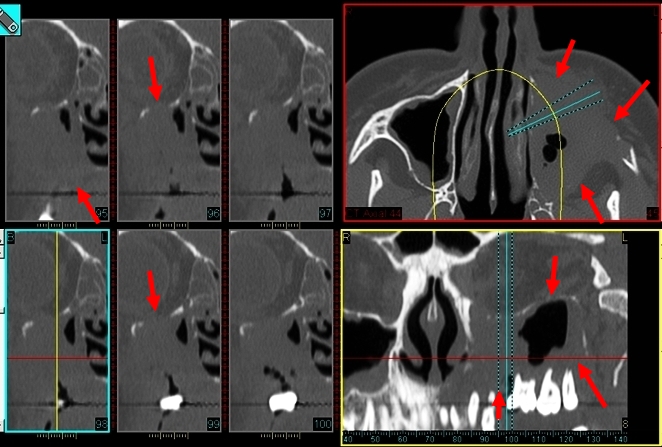

Une tumeur sinusienne maligne est cliniquement longtemps muette ou s’exprime de façon aspécifique par un dysfonctionnement naso-sinusien, une obstruction nasale ou une épistaxis spontanée. Ces signes plus souvent unilatéraux font pratiquer un CBCT, évocateur s’il montre une masse volontiers volumineuse, hétérogène, plus ou moins irrégulière et surtout lytique sur les parois naso-sinusiennes, et notamment du plancher sinusien et la fosse ptérygomaxillaire. Cet aspect fera discuter les pathologies tumorales malignes et pratiquer une endoscopie et une IRM. Le diagnostic est le plus souvent histologique, révélant les diagnostics suivants :

- Carcinome épidermoïde (Fig. 1) : c’est la plus fréquente des tumeurs malignes naso-sinusiennes, favorisée par l’exposition au nickel, à la poussière d’industrie du cuir ou du textile et au tabac. Touchant un peu plus l’homme que la femme autour de la soixantaine, il impose la réalisation d’une IRM avec injection pour le bilan d’extension locale (classification TNM) et vers la base du crâne, directement ou par extension perineurale rétrograde sur le trajet du nerf trijumeau.

- Lymphomes non Hodgkiniens (Fig. 2) : il s’agit essentiellement de lymphomes de type B à grandes cellules, diffus dans les sinus maxillaires avec atteintes ganglionnaires précoces et de lymphomes de type T/NK (Natural Killer), plus agressif, dans les fosses nasales. Leur aspect n’est pas spécifique en CBCT ou en IRM et leur diagnostic est surtout histologique.